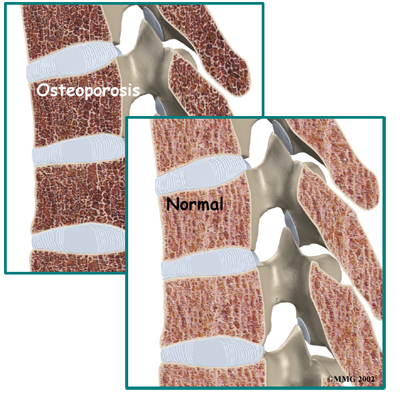

is a disease that weakens bone. Sometimes the bones in the spine weaken to the point that even mild forces can lead to a compression fracture. A simple action like reaching down to pull on a pair of socks can cause a weakened vertebra to fracture. The front of the vertebra (the part closest to the front of the body) crumbles, causing the round vertebral body to become wedge-shaped. This angles the spine forward, producing a hunch-backed appearance, called kyphosis.

Diseases or conditions that affect the parathyroid gland can also weaken bones. Four pea-sized parathyroid glands are located just behind the thyroid gland in the throat. They produce a substance called parathyroid hormone (PTH), which normally regulates the amount of calcium in the blood stream. An overactive parathyroid gland releases too much PTH, causing the body to leach calcium from bones, even when there is more than enough calcium circulating in the blood stream. This disorder is called hyperparathyroidism. It occurs when a tumor, called an adenoma, forms in one of the parathyroid glands. Cancers that affect the kidney, skin, or parathyroid gland may also cause the parathyroid gland to malfunction. If the problem isn't fixed, bones continue to lose calcium and eventually weaken. Weakening in the spine bones makes the vertebrae more prone to crack in front, as is typical with osteoporosis.